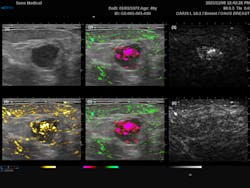

While some early clinical work had been performed by that time, PAI was still primarily used as a tool for basic biological research. Over the subsequent decade, PAI continued to evolve and has now been successfully demonstrated in a wide range of clinical applications—including breast, dermatological, and vascular imaging.3 2021 marked perhaps the most significant milestone when the Imagio breast imaging system (see Fig. 1) from Seno Medical (San Antonio, TX) became the first PAI system to cross the “valley of death” as the United States Food and Drug Administration (FDA) granted premarket approval.

The most common endogenous chromophores used in PAI application are oxyhemoglobin (HbO2) and deoxyhemoglobin (HHb). These are particularly interesting for tumor screening due to the increased metabolic activity within cancer cells. The Imagio breast imaging system was explicitly designed for that exact purpose, combining dual-wavelength PAI with traditional ultrasound to produce a false-color overlay of blood content over a grayscale ultrasound image. This system utilizes dual 757 nm and 1064 nm excitation lasers to take advantage of the relatively high absorption of HHb compared to HbO2 at 757 nm, as opposed to 1064 nm where the relative absorption flips. From Figure 2, we can see the traditional grayscale ultrasound image of the mass in the first image, along with a map of the total blood in yellow (image 4) and the differentiated HHb in red and HbO2 in green (images 2 and 5). For the first time, this system provides clinicians with an FDA-approved real-time noninvasive means of identifying cancers without the need for ionizing radiation.PAI offers a significant improvement over MRI for vascular imaging since it does not require external contrast agents. Laser speckle contrast imaging (LSCI) can also detect subdermal blood flow,5 but it does not provide the spatial resolution needed to map the vascular architecture, nor can it monitor oxygenation. That said, it should be noted that the speed and non-contact nature of LSCI compared to PAI make it attractive for specific applications such as real-time interoperative blood flow monitoring.